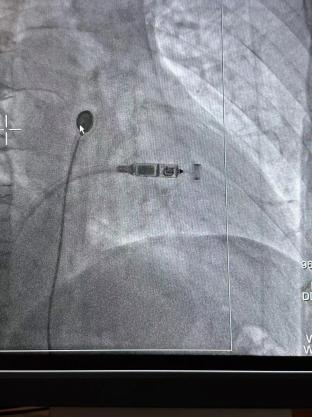

體積僅膠囊大小、重量?jī)H約2克,被譽(yù)為“全球體積最小的心臟起搏器”——Micra無導(dǎo)線心臟起搏器,近日在瀘州市中醫(yī)醫(yī)院投入臨床應(yīng)用。由瀘州市中醫(yī)醫(yī)院心血管內(nèi)科團(tuán)隊(duì)將其植入一名七旬老年患者心臟內(nèi),擔(dān)當(dāng)心臟“發(fā)動(dòng)機(jī)”作用。當(dāng)患者心跳過慢時(shí),通過發(fā)出起搏器電脈沖可使其恢復(fù)健康心跳頻率。

術(shù)前準(zhǔn)備充分后,李大爺在局部麻醉下行無導(dǎo)線心臟起搏器植入。心血管內(nèi)科醫(yī)生從大爺大腿根部?jī)H穿刺一個(gè)米粒粗細(xì)的小口,通過導(dǎo)管將起搏器植入心腔內(nèi)。該手術(shù)1個(gè)小時(shí)即順利完成,手術(shù)過程中大爺完全清醒,幾乎無疼痛感覺。

據(jù)悉,Micra無導(dǎo)線起搏器被稱為“全球最小的心臟起搏器”,其體積相比傳統(tǒng)心臟起搏器減小93%,重量約傳統(tǒng)起搏器的1/10。

該術(shù)式經(jīng)穿刺后直接植入在心腔內(nèi),無需在胸前皮下制作囊袋。無傷疤、無切口,患者恢復(fù)時(shí)間快,減少了創(chuàng)傷與感染風(fēng)險(xiǎn),大大改善了患者的生存質(zhì)量。